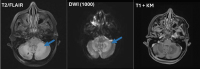

Abbildung 1: Patientin A: cMRT vom August 2023 (FLAIR-Sequenz, DWI-Sequenz, T1-Sequenz mit KM): subkortikale FLAIR-hyperintense und T1-hypointense Läsion rechts zerebellär (blaue Pfeile), mit randständig betonter Diffusionsrestriktion (grüner Pfeil), keine Kontrastmittelaufnahme